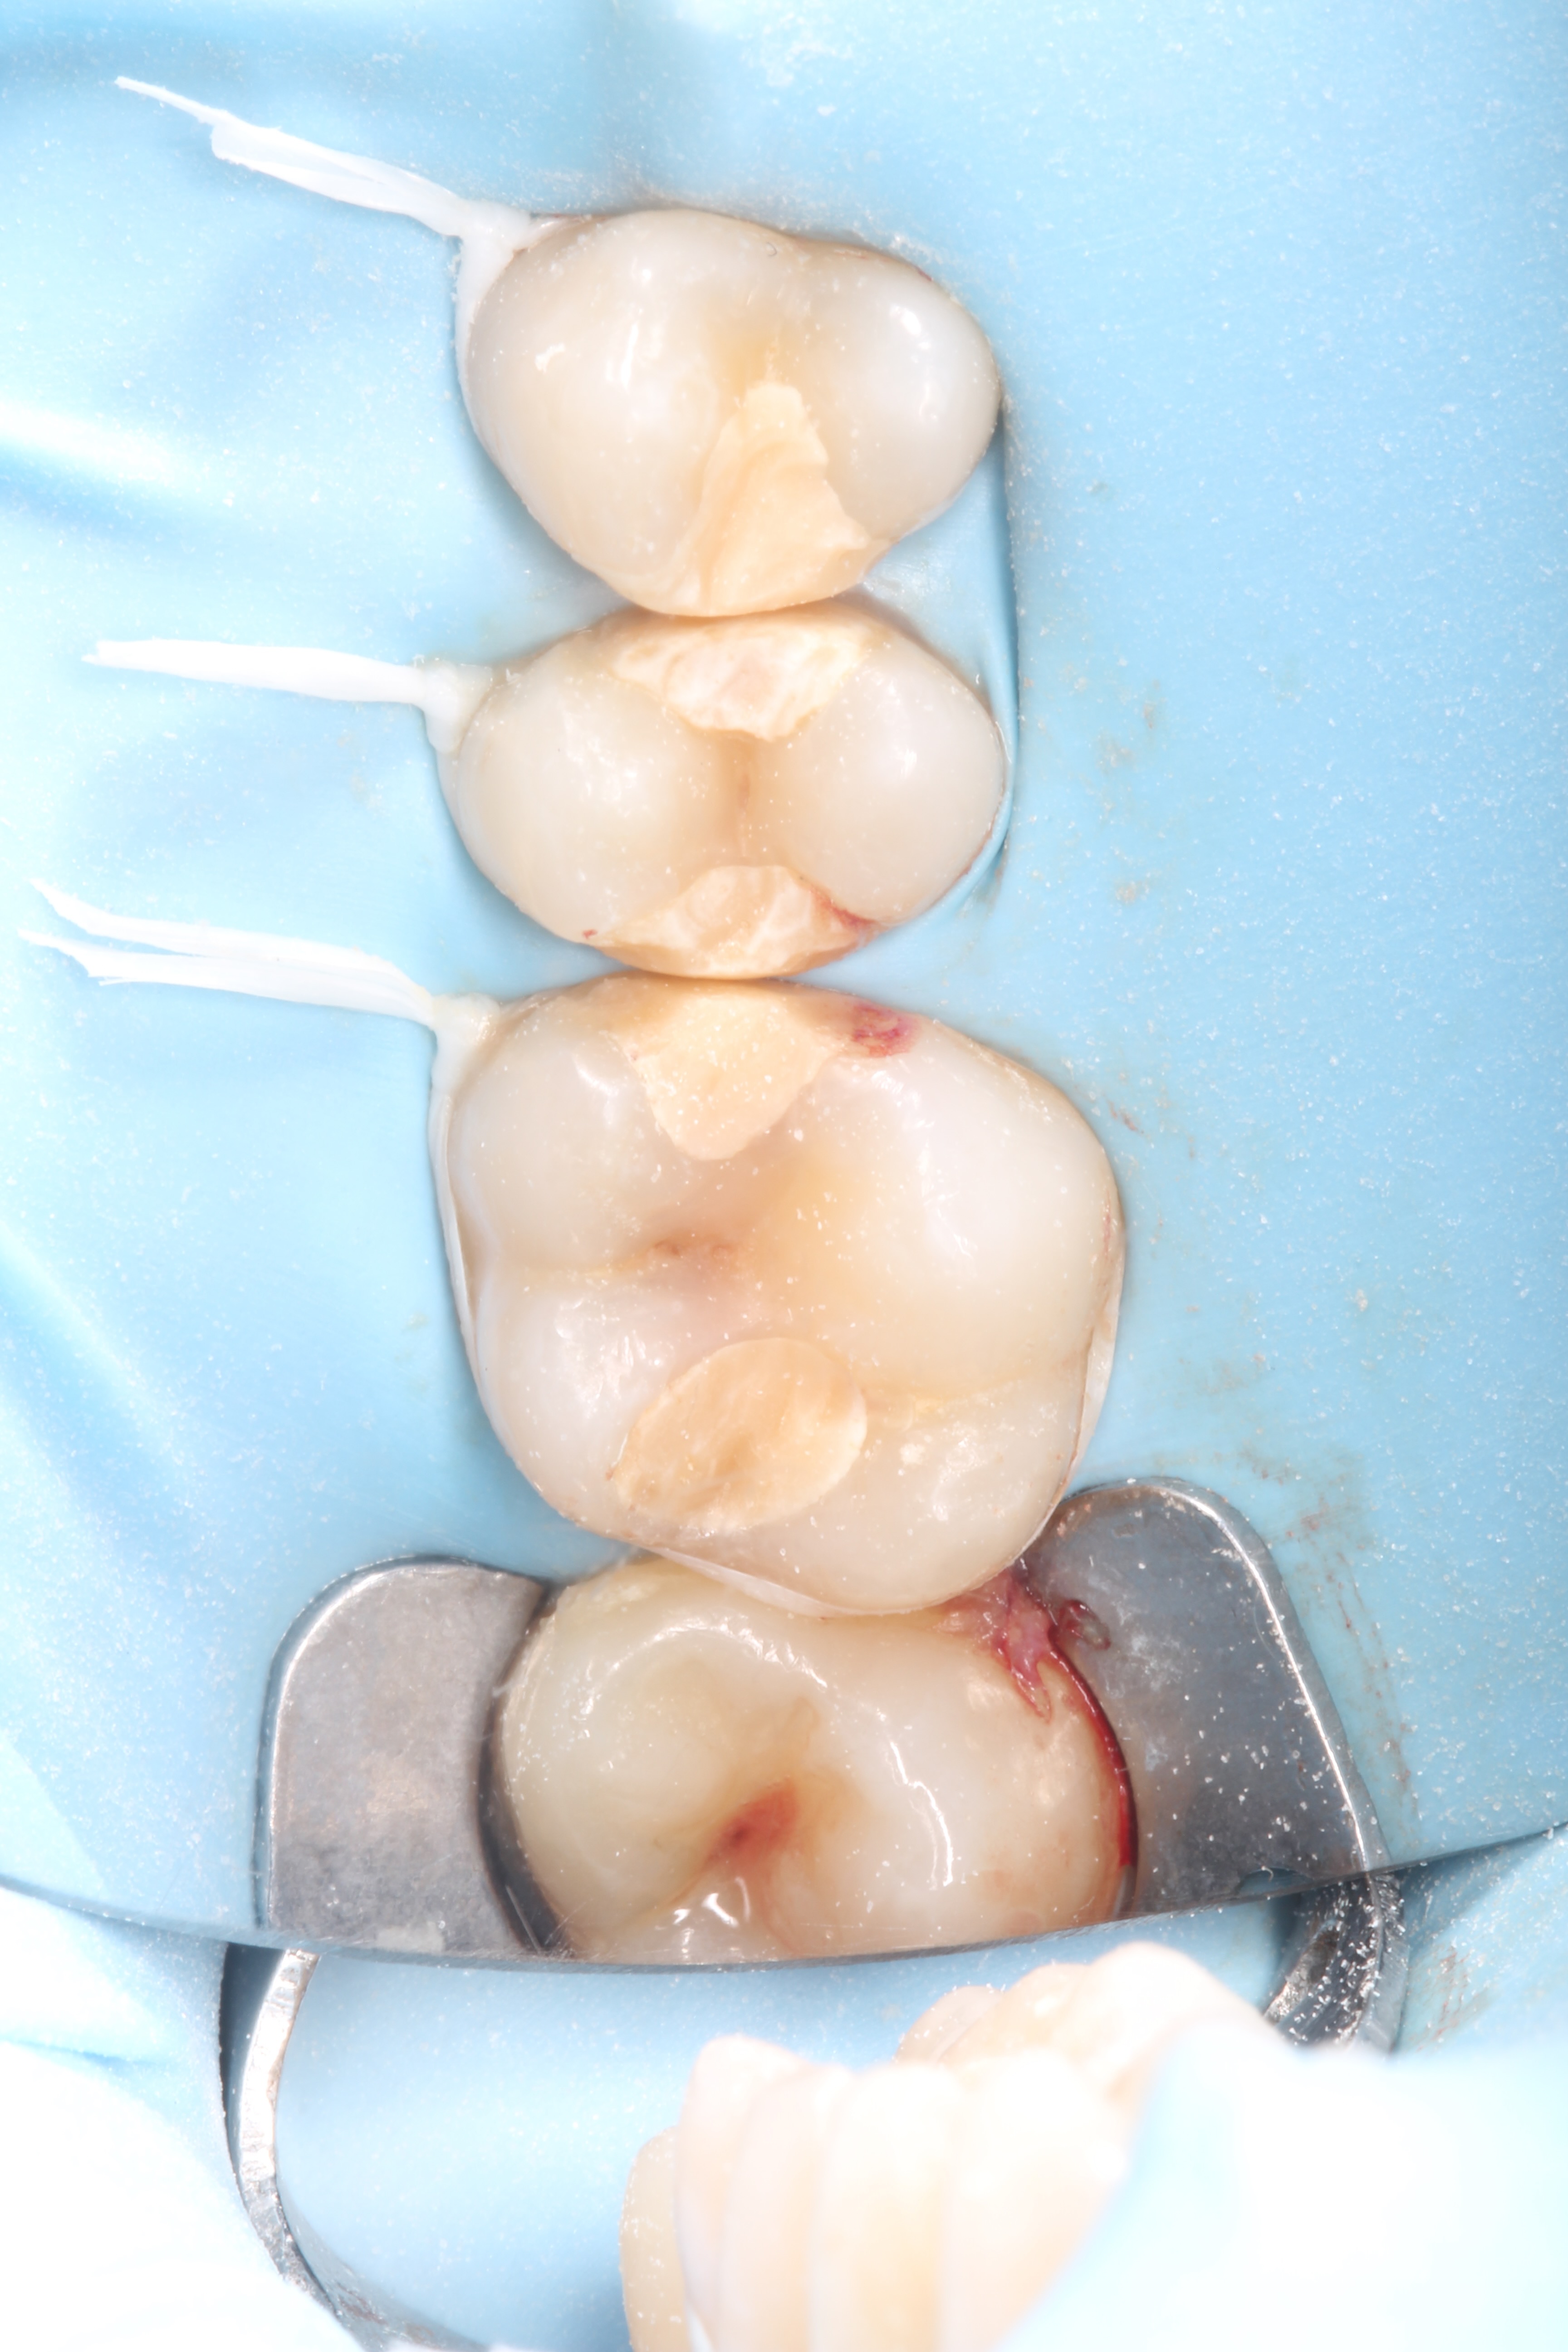

Crowns and onlays by Professor Brian Millar

This course solidified my knowledge and allowed me to practice various cuspal coverage treatments including overlays, onlays and vonlays. I was able to learn about the different preparation techniques and margins required for each indirect material.